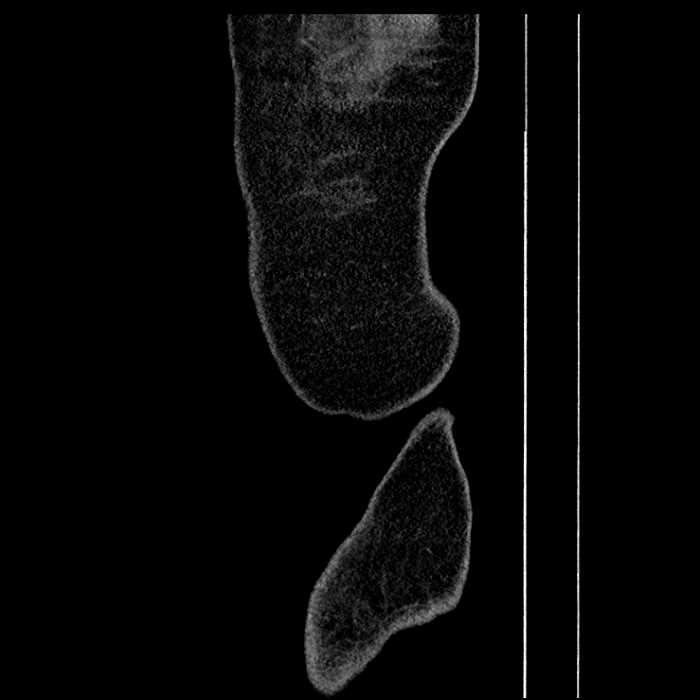

• Peripherally enhancing subcapsular collections along the anterior margin of the left hepatic lobe measuring 3 x 1 cm and 2 x 1 cm

Hepatic abscess showing the double target sign with low density internally surrounded by a thin inner enhancing rim (red arrow) and ill-defined outer low density rim (yellow arrow). Blue arrow indicates an internal septation. Red arrows: additional smaller subcapsular abscesses. Red arrow: focal contained perforation associated with diverticulitis.